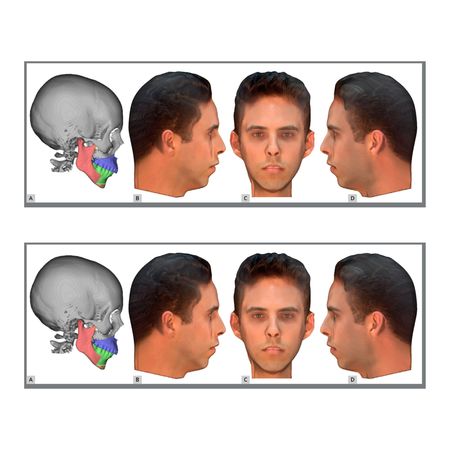

Objetivo: O objetivo deste estudo foi avaliar a percepção da atratividade facial em pacientes com Classe II esquelética e simular possíveis tratamentos para essa condição. Métodos: Foram utilizados escaneamentos dentários, escaneamentos faciais e tomografia computadorizada de feixe cônico (TCFC) de um paciente do sexo masculino. Essas imagens foram agrupadas em um software, onde o arquivo original foi editado para obter um perfil que apresentasse as características esqueléticas e...

Objective: The aim of this study was to assess the perception regarding the attractiveness of the face in patients with skeletal Class II and simulations of possible treatments for this condition. Methods: Dental scans, face scans and cone beam computed tomography (CBCT) of a male patient were used. These images were grouped in a software, where the original file was edited in order to achieve a profile that had the most pronounced skeletal and dental Class II (division 1) features, as well...